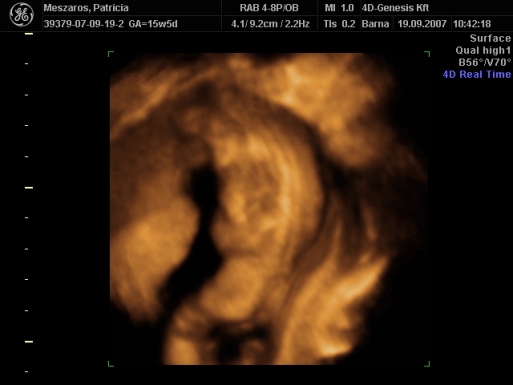

Üdv az újaknak! Itt valóban nagyon parás kismamák vannak, én az első 12 hetet végigparáztam, utána már csak mértékkel, de amióta mozog a bébi, meg láttam 4D-n, azóta oltári nyugodt vagyok...

Délután megyek a dokimhoz, terhesgondozásra, most kapok időpontot a következő UH-ra. Szerintem két hét múlva megyek, mert jövő héten sulihetem lesz, úgyhogy az kilőve. De most annyira nem is sürget a dolog, mivel a múlt héten volt a 4D.

Én is ajánlom mindenkinek a 4D-t, mi is nagyon jó helyet fogtunk ki, de mi vidéken, Szombathelyen voltunk, az van közel.

Egyébként mint megtudtam, ez a rendelő a Telki Magánkórház partnerintézete. Mondjuk elég luxus szinten mennek a dolgok, az biztos. De főleg az volt jó, hogy a szonográfus nő tök profi volt, és nagyon jól elmondott mindent, szinte minden részét láthattuk a kis kincsünknek, és még a nemét is megtudtuk kb. 9 perc után.

Szóval én nagyon meg voltam elégedve a szolgáltatással, egyébként 20 perces vizsgálat volt, szívhangot kihangosították, minden részét alaposan megnézték, kaptunk DVD-t, meg postán kapunk fényképeket. És ez volt 12.000 Ft.